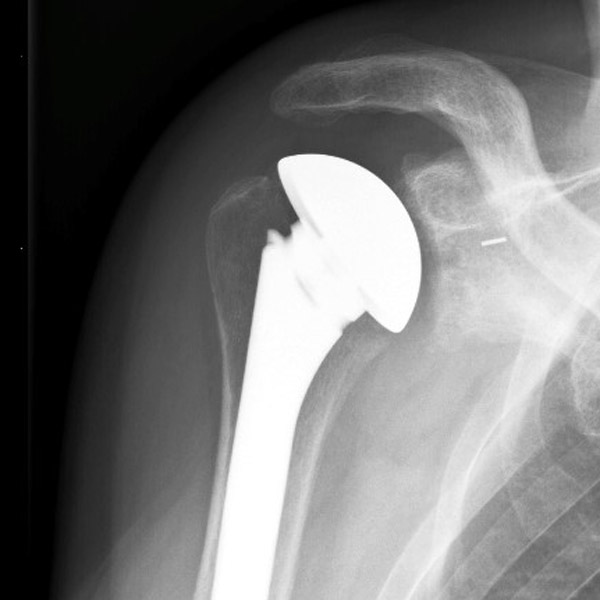

De anatomische schouderprothese

We plaatsen een anatomische schouderprothese wanneer het gewricht zelf versleten is, maar de pezen nog goed van kwaliteit zijn. Hierbij worden de bol en de kom vervangen. Deze prothese komt nauw overeen met het natuurlijke gewricht. Daarom heet deze prothese een anatomische prothese.De halve- of hemiprothese

De hemiprothese wordt geplaatst wanneer alleen de bol is aangetast, maar niet de kom. Alleen de bol wordt vervangen, de kom van het gewricht wordt niet vervangen.De omgekeerde prothese

Dit heet ook een niet- anatomische prothese omdat deze omgekeerd geplaatst wordt. Dus de bol van de prothese komt terecht op de kom en in plaats van de kom wordt een bol geplaatst. We gebruiken deze prothese wanneer de slijtage van de schouder het gevolg is van een lang bestaande rotator cuff scheur of wanneer de pezen van de rotator cuff niet gehecht kunnen worden. In dat geval is de anatomische prothese niet toereikend genoeg.